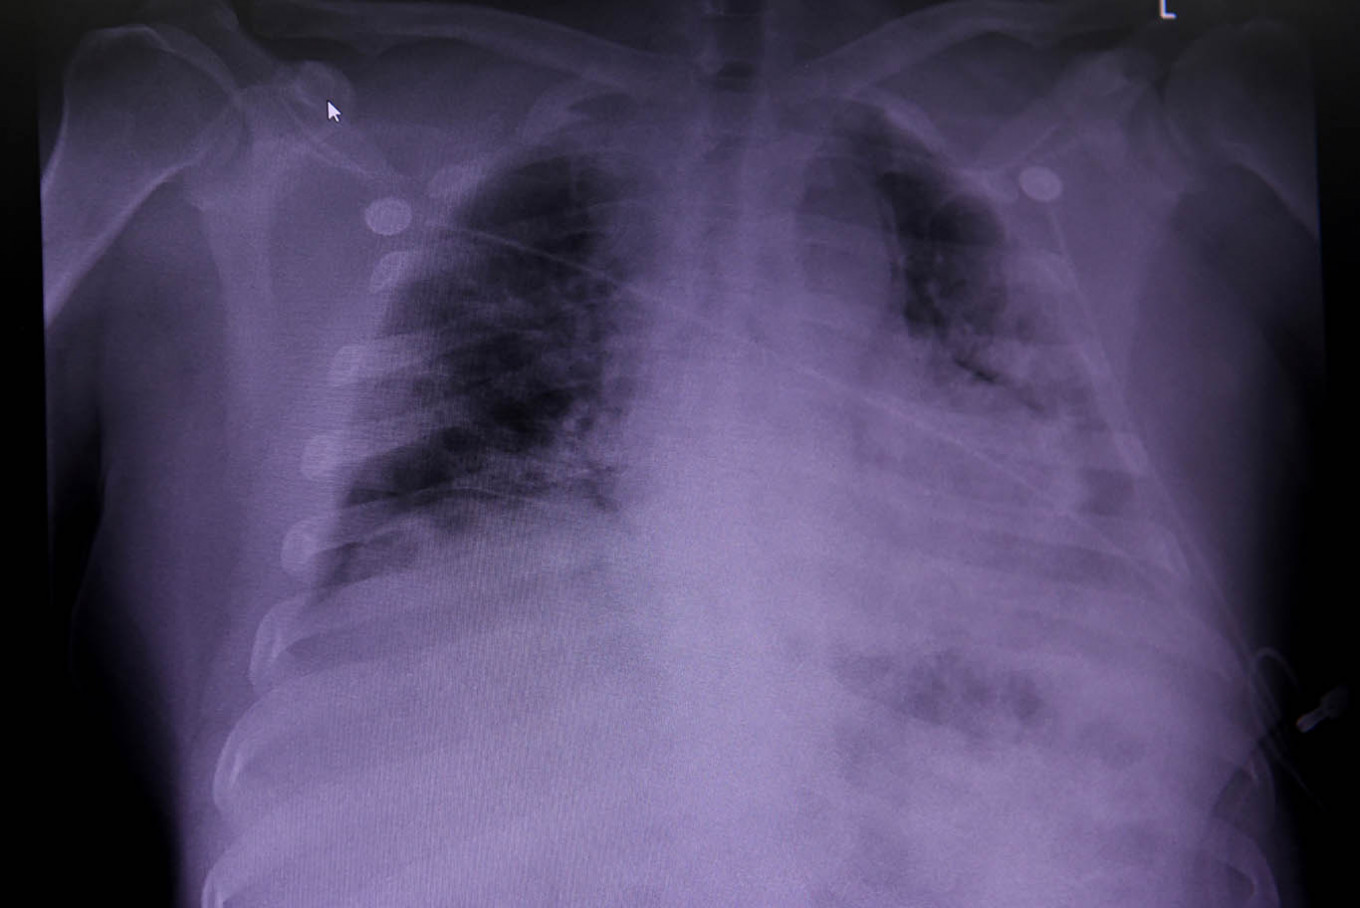

An X-ray of a COVID-19 patient's lungs at United Memorial Medical Center in Houston, Texas, United States, on July 10, 2020.  An X-ray of a COVID-19 patient's lungs at United Memorial Medical Center in Houston, Texas, United States, on July 10, 2020. (REUTERS/Callaghan O'Hare/File Photo)

study of the lungs of people who have died from COVID-19 has found persistent and extensive lung damage in most cases and may help doctors understand what is behind a syndrome known as 'long COVID', in which patients suffer ongoing symptoms for months.

In a telephone interview, Giacca said that, while his research team found no overt signs of viral infection or prolonged inflammation in other organs, they discovered "really vast destruction of the architecture of the lungs", with healthy tissue "almost completely substituted by scar tissue".

"It could very well be envisaged that one of the reasons why there are cases of long COVID is because there is vast destruction of lung (tissue)," he told Reuters. "Even if someone recovers from COVID, the damage that is done could be massive."

Giacca said almost 90 percent of the 41 patients had several characteristics unique to COVID-19 compared to other forms of pneumonia.

One was that patients had extensive blood clotting of the lung arteries and veins. Another was that some lung cells were abnormally large and had many nuclei - a result of the fusion of different cells into single large cells in a process known as syncytia.